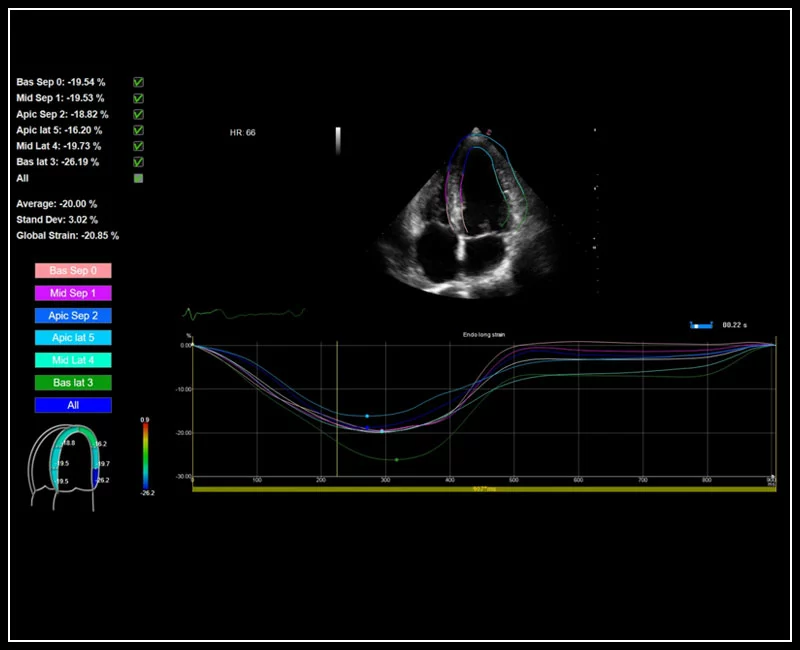

MyLab™9 Platform - XStrain™ 2D speckle tracking technologies for global and regional function

MyLab™9 Platform - XStrain™ 2D speckle tracking technologies for global and regional function